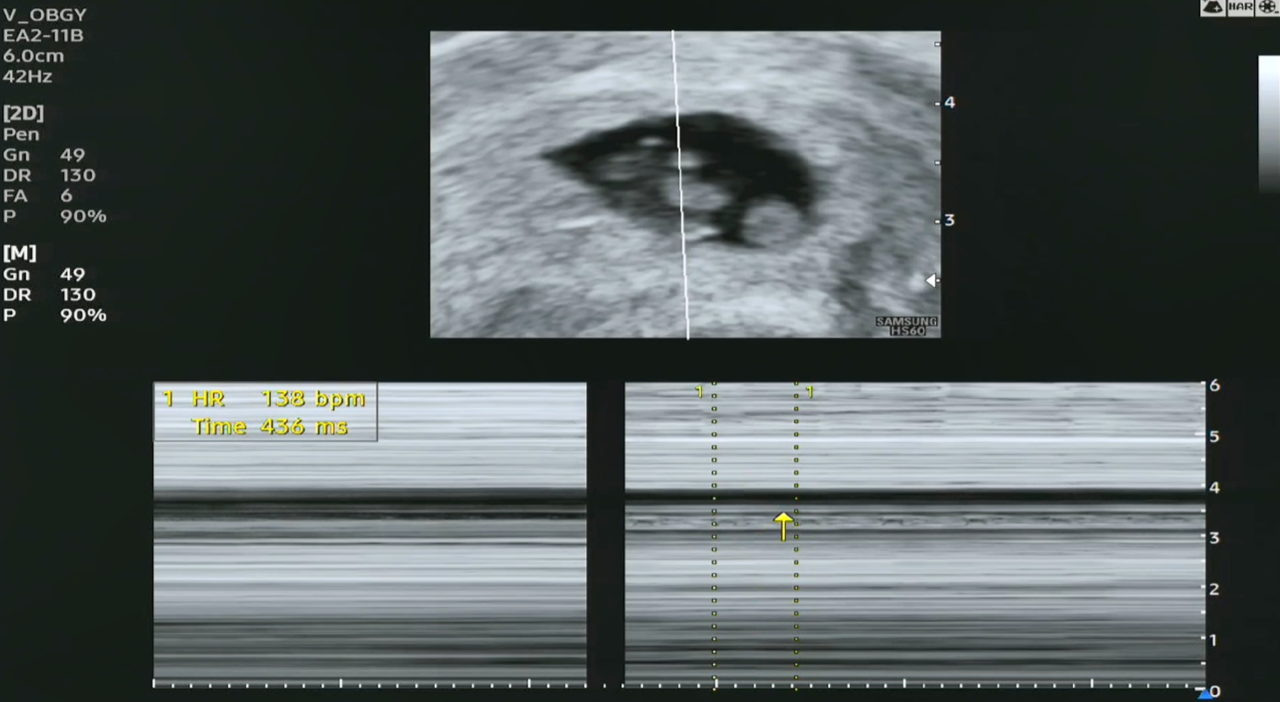

검사한 결과, 태아의 심박수는 138 bpm이라고 보이네요. 아직 7주 0일 차라서 그런 것 같습니다.

인터넷에서 보니 임신 6.2주에 약 110 bpm에서 7.0~8.0주에 약 159 bpm으로 점차 증가한다고 합니다. 그리고 9주까지는 140~170 bpm 정도로 증가하는 것이 일반적이라고 하는데, 태아마다 이 범위가 조금씩 높거나 낮을 수 있다고 하네요. 이 기준에 따르면 태아는 매우 정상적인 심박수인 것으로 보입니다.

태아 심장 박동수 캡쳐.png [심박수 캡처 화면]

[심박수 초음파 영상]